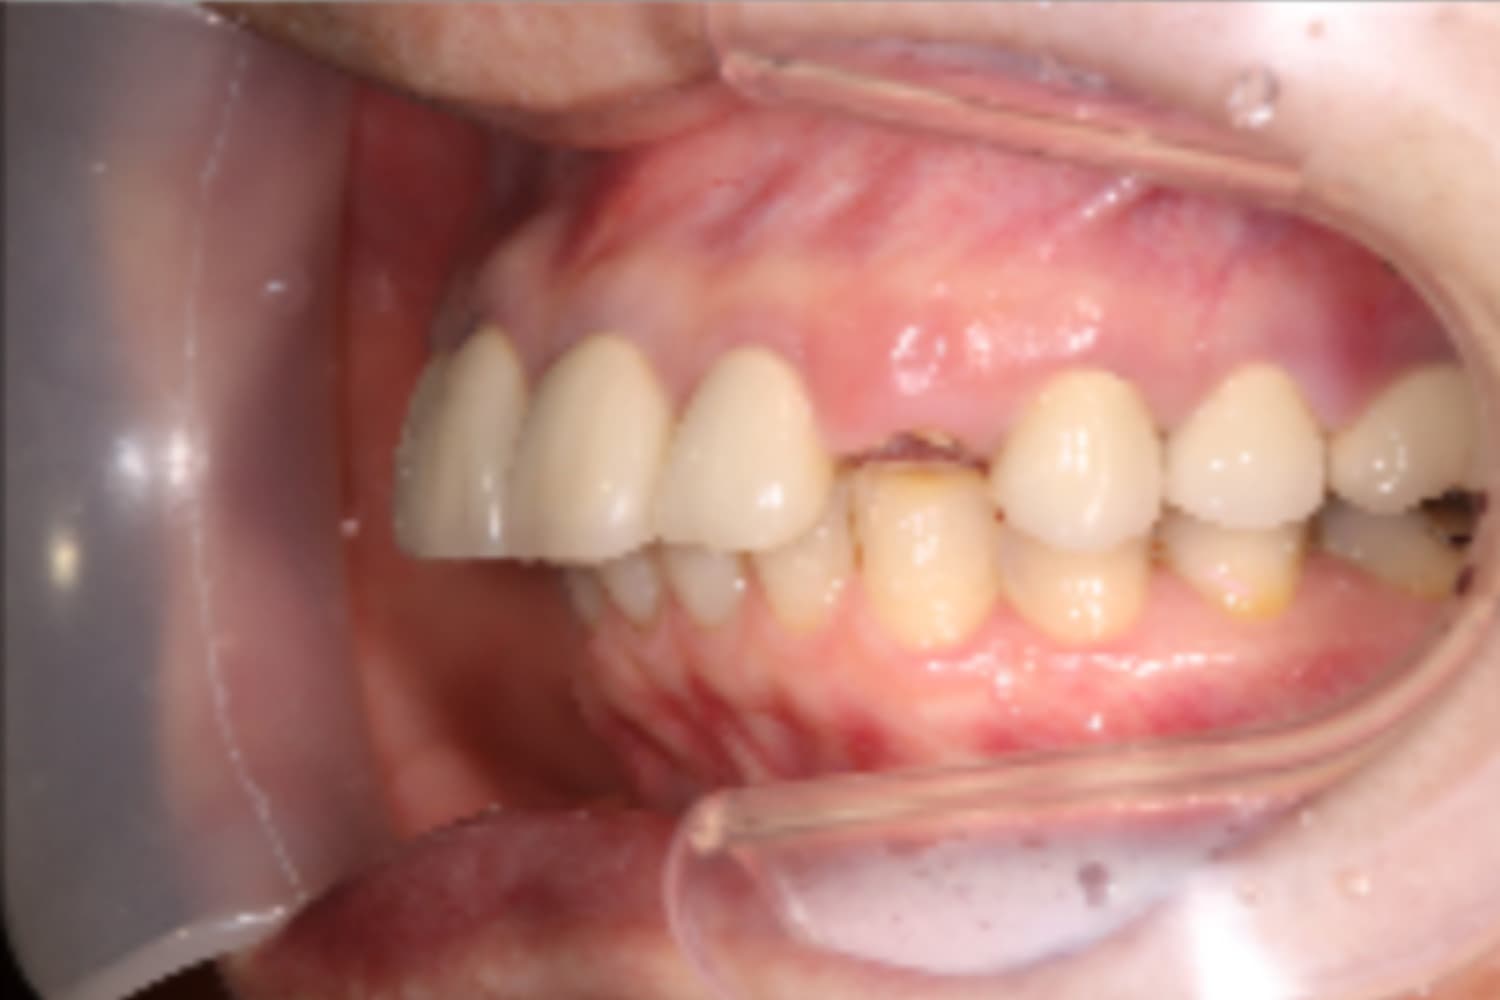

左上前歯のインプラント治療

Before

After

変色している歯は、根が割れているため抜歯し、インプラント治療を行なった。

主訴

左上前歯の変色

治療期間

5カ月

治療回数

10回

費用

533,500円

副作用・リスク

・抜歯と同時にインプラントを埋入するためで初期固定が得にくく、治癒期間が延長する可能性があります ・感染症のリスクがあります。